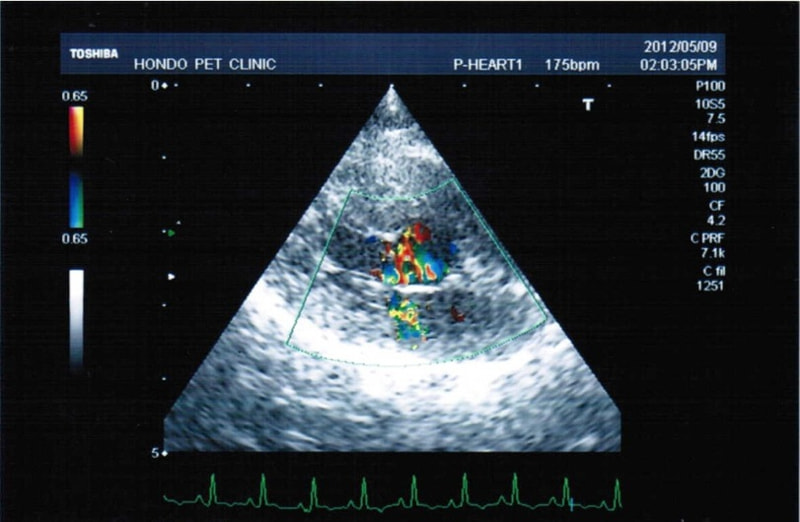

症例6:【ACVIM StageD ビーグル 10歳 去勢雄】

C:超音波 僧帽弁逆流のカラードップラー画像

左側胸壁心尖部領域を最強点とするLevine 5/6の収縮期性心雑音が聴取された。安静時にも咳が認められる。胸部レントゲン検査において重度の心拡大が及び肺水腫が認められた。超音波検査では、重度の僧帽弁閉鎖不全、三尖弁閉鎖不全が認められた。三尖弁逆流速度から肺高血圧症が示唆された。ACE阻害薬、ピモベンダン、硝酸イソソルビド徐放剤、ベラプロストナトリウム、利尿剤としてフロセミド及びスピロノラクトンを用いて治療を行っている。